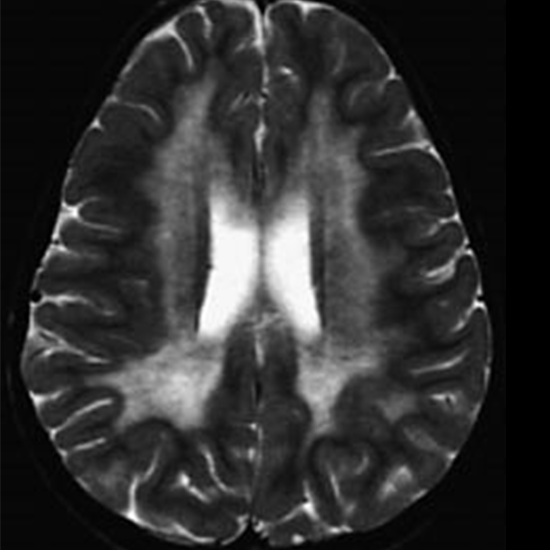

Metachromatic Leukodystrophy is an uncommon hereditary illness that causes fatty substances to accumulate in cells, especially in the brain, spinal cord, and peripheral nerves. A lack of sulfatides, an enzyme that aids in the breakdown of lipids, results in this accumulation.

Metachromatic Leukodystrophy Quantitative Test is to detect and diagnose the deficiency of an enzyme that causes metachromatic leukodystrophy and to check sulfatide levels.